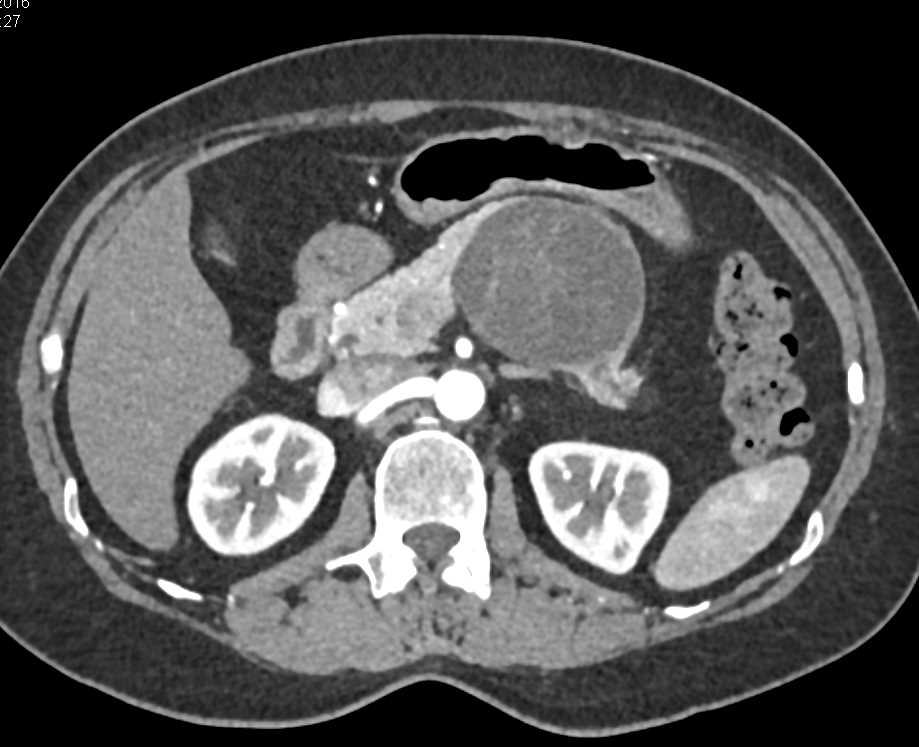

1cm Pancreatic Neuroendocrine Tumor (PNET) in the Head of the Pancreas